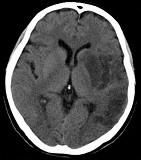

- 单项选择题男,62岁, 8小时前患者突发右侧肢体瘫痪1天,构音不清, CT检查如图,最可能的诊断是 ( )

A、脑梗死

B、星性胶质瘤

C、脑脓肿

D、少突胶质细胞瘤

E、血管母细胞瘤